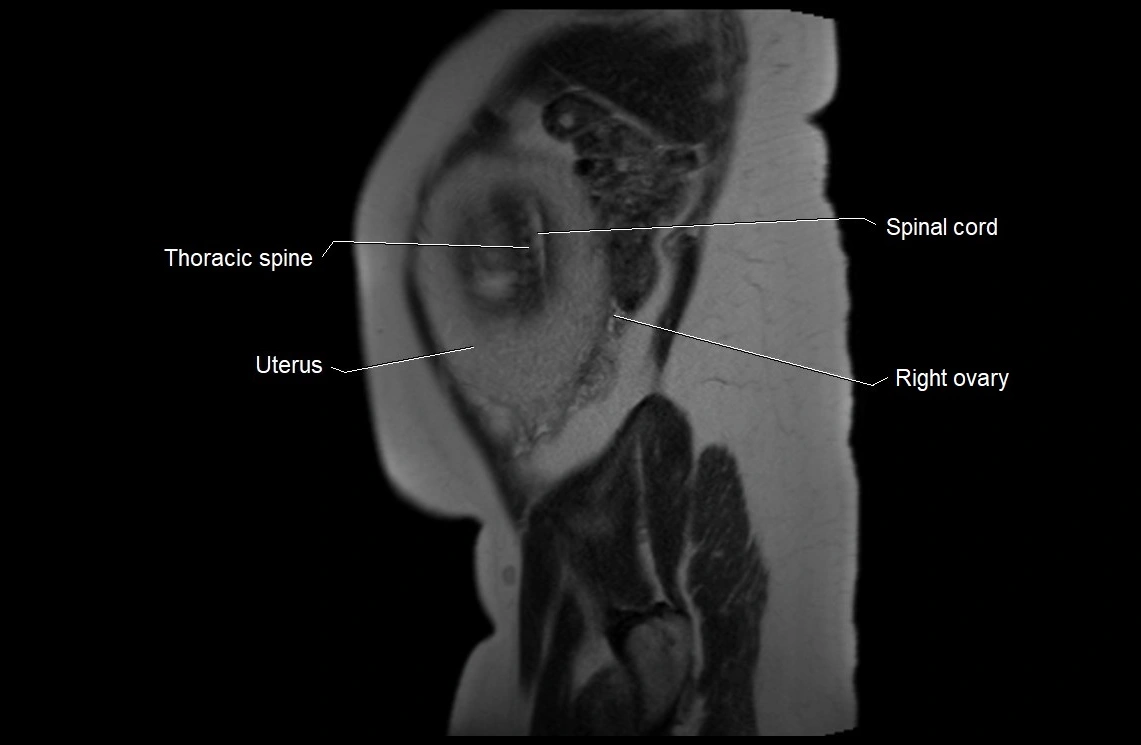

MRI image

image